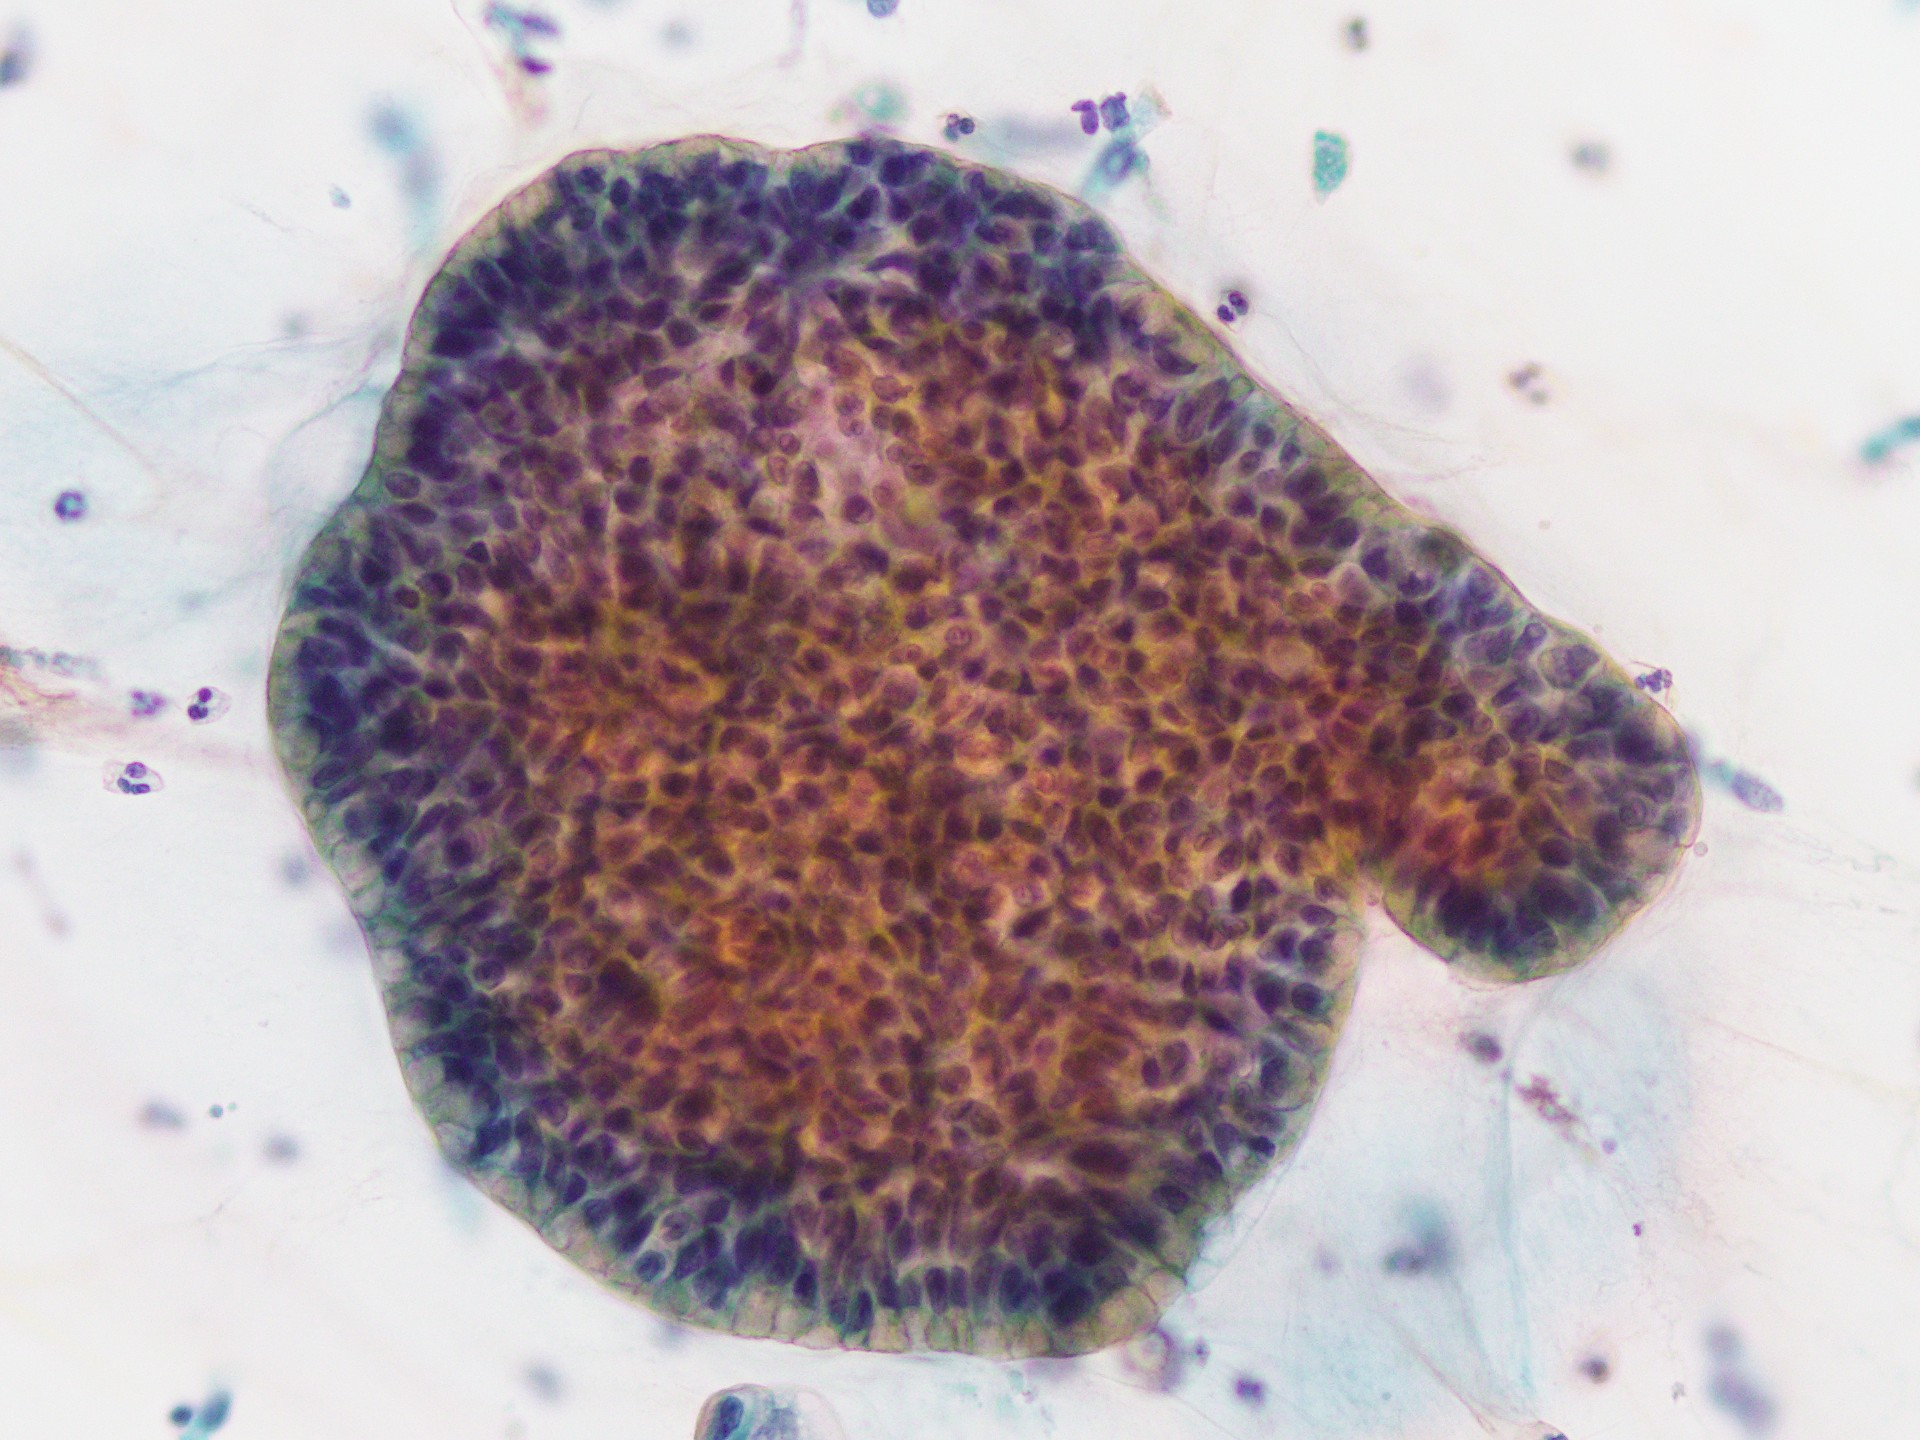

解答:浸潤性粘液産生性腺癌

一般的に多量の粘液を背景に高円柱状で豊富な細胞質内粘液を有する細胞が、

シート状もしくは乳頭状集塊として出現しています。

核は小型で、粘液の存在により基底部に位置しています。

核異形は通常軽度なことが多く、杯細胞集塊や過形成として認識してしまう可能性があり、

スクリーニングでの見落としに注意が必要と考えます。

PAP×10 PAP×40 PAP×10 PAP×40